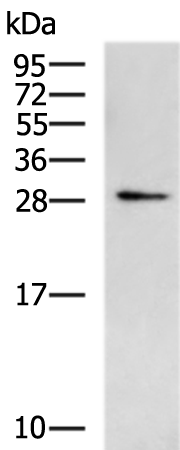

分类: 科研抗体货号: P10690别名: TIM; KIM1; TIM1; CD365; HAVCR; KIM-1; TIM-1; TIMD1; TIMD-1; HAVCR-1应用: WB,IHC反应种属: Human

分类: 科研抗体货号: P10678别名:应用: WB,IHC反应种属: Human, Mouse, Rat